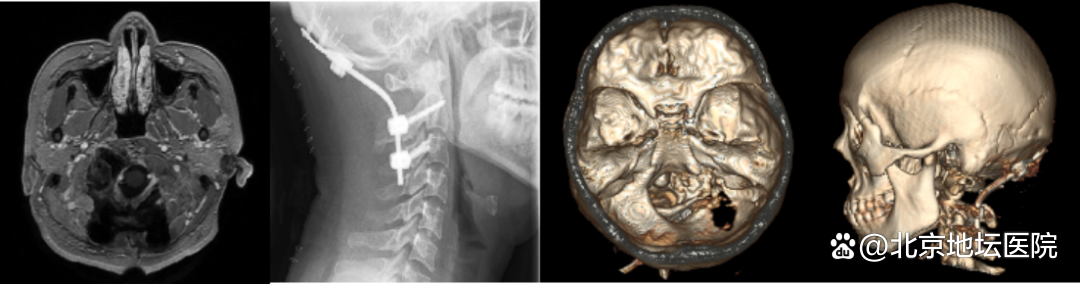

神外团队联合麻醉科及复合手术室进行了充分的术前讨论,决定采用复合手术的方式完成手术。计划先由神外的血管介入组建立动脉通路,以应对术中椎动脉破裂等突发情况,为手术顺利进行保驾护航。同时,脑肿瘤组行远外侧入路切除颅内肿瘤,最后由脊髓脊柱组行枕颈融合内固定术完成手术。

手术当天,神经外科团队医生、麻醉科、复合手术室均准备就绪。患者全麻插管后,副主任医师李风志熟练地完成动脉通路建立。紧接着,主任医师冯恩山、梁博及医师杨博等医生开始了肿瘤切除。同术前判断的一致,肿瘤已完全侵袭枕髁骨质、患者颈椎的稳定性受到严重破坏。

肿瘤被切除后,冯恩山及主治医师王小永对患者的枕颈部进行内固定,保证头部的稳定性。令人欣慰的是,手术过程中没有出现大出血、各分支血管及颅神经也都被完整地保留下来。

术后第二天,小兰已经可以下地活动和正常进食了,咳嗽反射也表现良好。术后复查头CT、MRI及颈部平片示术区无出血、肿瘤完整切除;枕颈固定装置位置及颈椎曲度均良好。